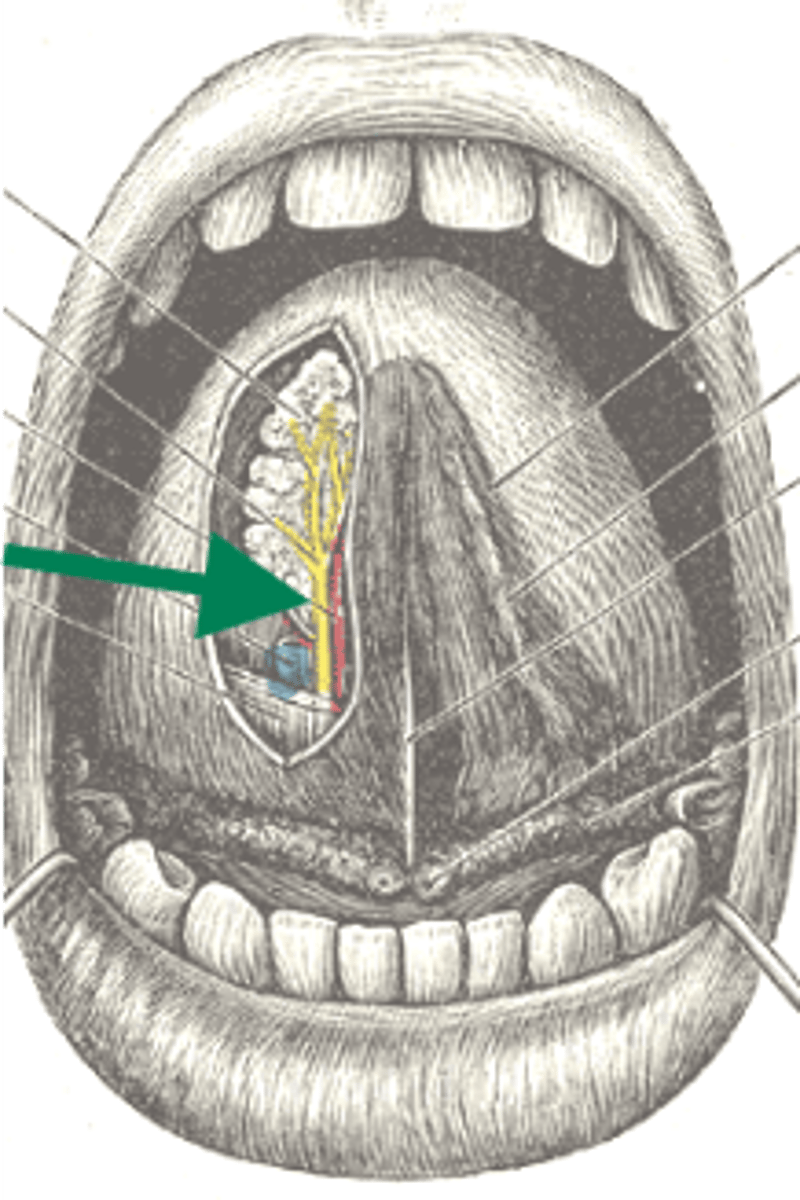

lingual nerve

lingual artery

lingual vein

lingual nerve

genioglossus

geniohyoid

mylohyoid

lingual artery

lingual nerve